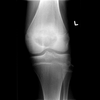

What are the 4 typical characteristics of giant cell tumours?

- Only in patients with closed epiphyses

- The lesion must be epiphyseal and abut the articular surface- not in flat bones.

- Eccentrically located

- Must have a sharply defined zone of transition (border) that is not sclerotic.

Not in flat bones. BUT can be in spine and SACRUM